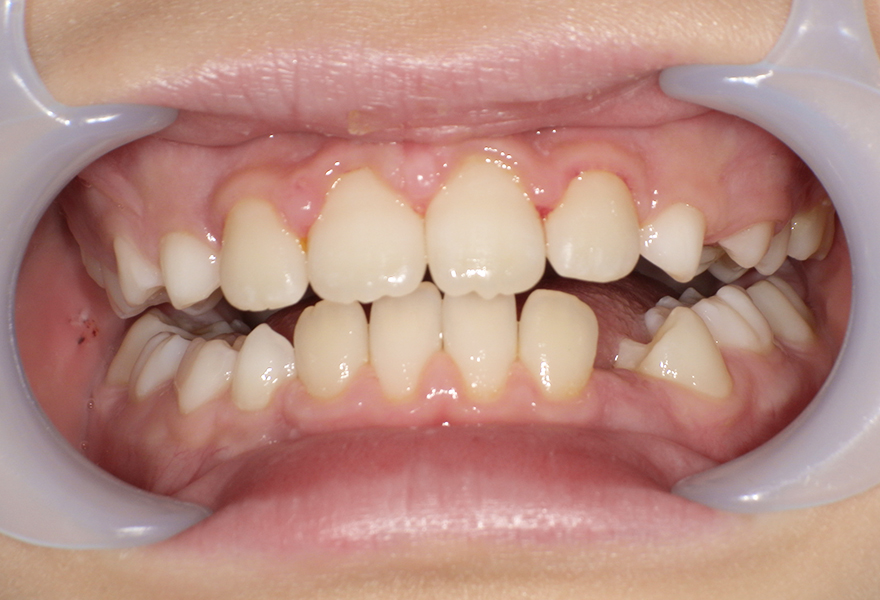

小児矯正(MRC)により歯列と咬合を改善した症例(8歳女児)

治療後 ![]() |

10歳10か月時点で、歯列の幅が広がり、前歯の重なりが改善されました。上下の噛み合わせも安定し、永久歯が並ぶためのスペースが確保されています。口元の見た目が整っただけでなく、清掃性も向上しています。 |

約2年7か月(Ⅰ期治療) |

成長期のお子さまは、顎の発育をコントロールしながら歯並びを整えることが可能です。本症例では、早期に介入することで、将来的な抜歯矯正のリスクを減らし、自然な歯列発育を促すことができました。歯並びや噛み合わせが気になる場合は、できるだけ早めのご相談をおすすめします。 |